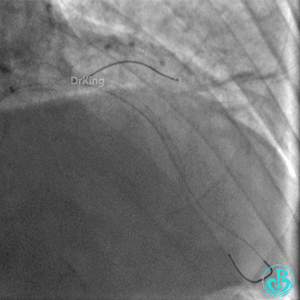

钝缘支经微导管释放5.0×5.5mm弹簧圈封堵破口。

明胶在血管怎么降解并发症丨前降支CTO同侧逆向开通时侧支血管破裂,弹簧圈联合明胶海绵封堵_https://www.jmylbn.com_新闻资讯_第34张

明胶在血管怎么降解并发症丨前降支CTO同侧逆向开通时侧支血管破裂,弹簧圈联合明胶海绵封堵_https://www.jmylbn.com_新闻资讯_第35张

双向弹簧圈封堵后观察30分钟,病情稳定,渗漏似乎减少,返回病房。